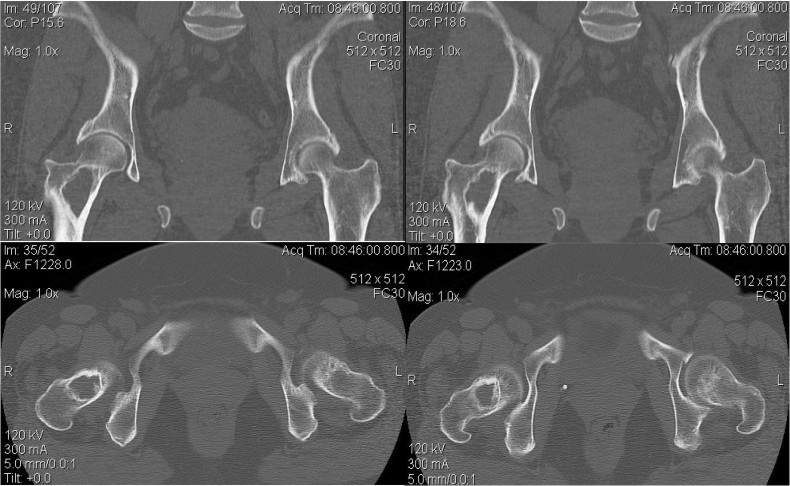

Обратилась пациентка 48 лет с жалобами на боль в области правого тазобедренного сустава, усиливающуюся при ходьбе. Купирует болевые ощущения приемом нестероидных противовоспалительных препаратов, при ходьбе пользуется тростью. Амплитуда движений несколько ограничена болевыми ощущениями за счет отведения и ротации. На выполненных КТ - киста, практически тотально поражающая шейку бедренной кости.

Учитывая хорошее, на наш взгляд, состояние тазобедренного сустава планируем выполнить экскохлеацию кисты, пластику полости аутокостью и фиксацию динамической бедренной системой. Смущает большой размер полости... Насколько критично плотное заполнение полости трансплантатом? Может быть будет достаточно поместить трансплантат из плотной компактной кости по дуге Адамса? Можно ли использовать в такой ситуации синтетические материалы, не секвестрируются ли они со временем?  Или же однозначно эндопротезирование? Будем рады услышать мнение и критические замечания, которые помогут принять верное решение.